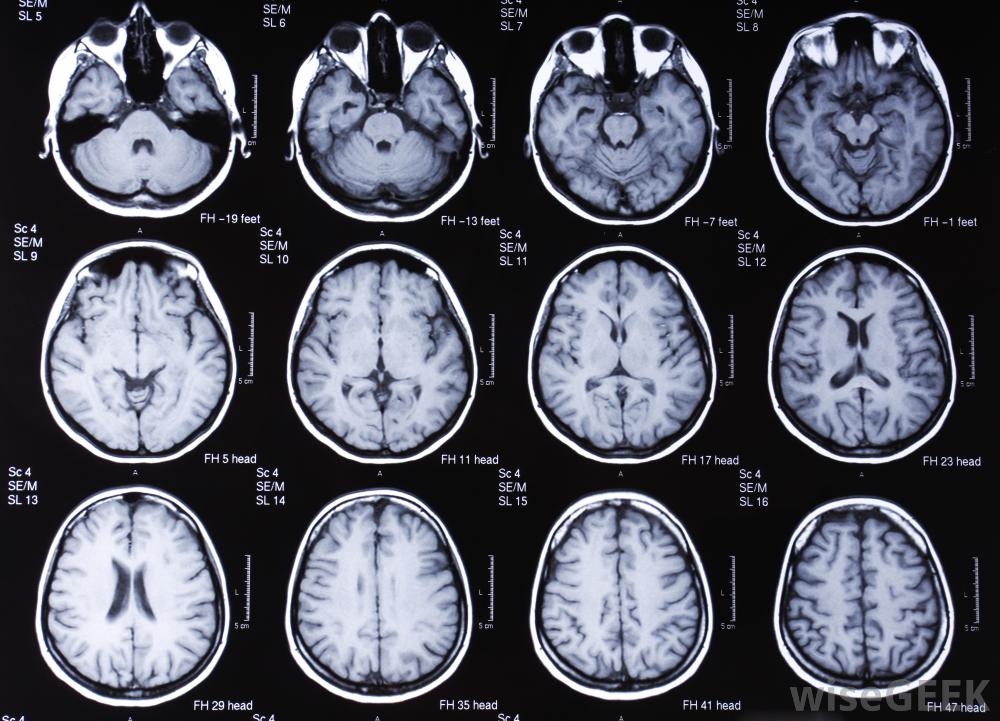

顯微共振成像(MRI)掃描是現代醫學中常用的診斷工具。雖然核磁共振成像通常不痛,但一些患有嚴重幽閉恐懼癥或無法保持靜止狀態的患者可能會要求或被處方一種鎮靜劑,以便在掃描前服用。MRI的鎮靜作用通常不是全部的,而是相反使病人處于輕微的鎮靜狀態。放射科醫生可能比緊張或焦慮的病人得到更好的結果核磁共振成像的工作原理是將人體的水分子排列成一個三維的身體圖像。這個過程需要在機器中幾乎完全靜止,因為移動會扭曲圖像。核磁共振成像的鎮靜劑可以幫助慢性疼痛患者放松在掃描過程中,通過減少他們移動或移動的需要。對大腦進行核磁共振掃描核磁共振檢查前的鎮靜劑對藥物治療或疾病導致的抽搐或抽搐也有幫助,如不寧腿綜合征。核磁共振的鎮靜劑可以使病情平靜足夠長時間,以獲得必要的圖像。通常,口服鎮靜劑用于核磁共振掃描,但在更嚴重的情況下,靜脈滴注鎮靜劑或吸入鎮靜劑可使患者處于更深層的鎮靜狀態許多病人在做核磁共振之前都會被輕微的鎮靜劑。另一個原因是幽閉恐懼癥。核磁共振機器看起來像一個狹窄的管子,會引起病人的反應對小地方有明顯恐懼的人。掃描也可能需要一個小時,這取決于需要的圖像量,所以那些有焦慮或幽閉恐懼癥的人需要能夠長時間安靜地躺著。對于那些不相信自己可以保持靜止或在狹小空間內出現恐慌癥狀的人,鎮靜劑核磁共振成像可能是有用的。除了使病人平靜下來,它還可以使檢查比病人移動或驚慌更快。核磁共振成像的工作原理是調整身體的水分子做核磁共振檢查時,孩子們也可能需要服用鎮靜劑。雖然進行了安全無痛的掃描,但機器和無法移動可能會讓一些年輕的患者感到恐懼。父母不能和孩子一起去做核磁共振檢查,這種恐懼可能會更加嚴重核磁共振室,盡管大多數核磁共振掃描儀都有一個麥克風,如果有問題的話,病人可以和控制室通話。在核磁共振成像中服用鎮靜劑時,必須仔細遵守醫生的指示有些表格要求病人在服藥前數小時內不得進食或飲水。由于極度困倦是一種常見的副作用,服用鎮靜劑的人不能獨自開車回家,通常在手術后幾個小時內必須被監測有無并發癥的跡象鎮靜可通過靜脈滴注進行。